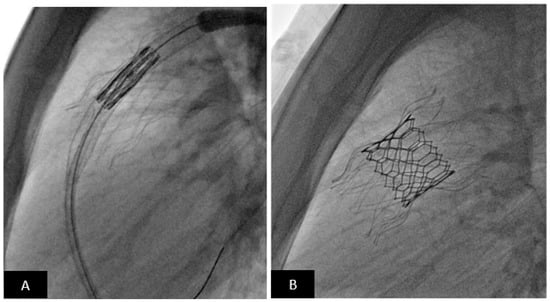

- Abdullah, H.A.M.; Alsalkhi, H.A.; Khalid, K.A. Transcatheter closure of sinus venosus atrial septal defect with anomalous pulmonary venous drainage: Innovative technique with long-term follow-up. Catheter. Cardiovasc. Interv. 2020, 95, 743–747. [Google Scholar] [CrossRef] [PubMed]

- Rosenthal, E.; Qureshi, S.A.; Jones, M.; Butera, G.; Sivakumar, K.; Boudjemline, Y.; Hijazi, Z.M.; Almaskary, S.; Ponder, R.D.; Salem, M.M.; et al. Correction of sinus venosus atrial septal defects with the 10 zig covered Cheatham-platinum stent—An international registry. Catheter. Cardiovasc. Interv. 2021, 98, 128–136. [Google Scholar] [CrossRef]